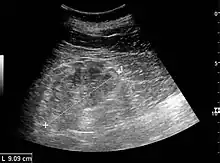

The kidney is divided into parenchyma and renal sinus. The renal sinus is hyperechoic and is composed of calyces, the renal pelvis, fat and the major intrarenal vessels. In the normal kidney, the urinary collecting system in the renal sinus is not visible, but it creates a heteroechoic appearance with the interposed fat and vessels. The parenchyma is more hypoechoic and homogenous and is divided into the outermost cortex and the innermost and slightly less echogenic medullary pyramids. Between the pyramids are the cortical infoldings, called columns of Bertin (Figure 1). In the pediatric patient, it is easier to differentiate the hypoechoic medullar pyramids from the more echogenic peripheral zone of the cortex in the parenchyma rim, as well as the columns of Bertin (Figure 2).[1]

Figure 1. Normal adult kidney. Measurement of kidney length on the US image is illustrated by ‘+’ and a dashed line. *Column of Bertin; ** pyramid; *** cortex; **** sinus.[1]

The length of the adult kidney is normally 10–12 cm, and the right kidney is often slightly longer than the left kidney. The adult kidney size is variable due to the correlation with body height and age; however, normograms for pediatric kidney size are available.[1]

Cortical thickness should be estimated from the base of the pyramid and is generally 7–10 mm. If the pyramids are difficult to differentiate, the parenchymal thickness can be measured instead and should be 15–20 mm (Figure 3). The echogenicity of the cortex decreases with age and is less echogenic than or equal to the liver and spleen at the same depth in individuals older than six months. In neonates and children up to six months of age, the cortex is more echogenic than the liver and spleen when compared at the same depth.[1]